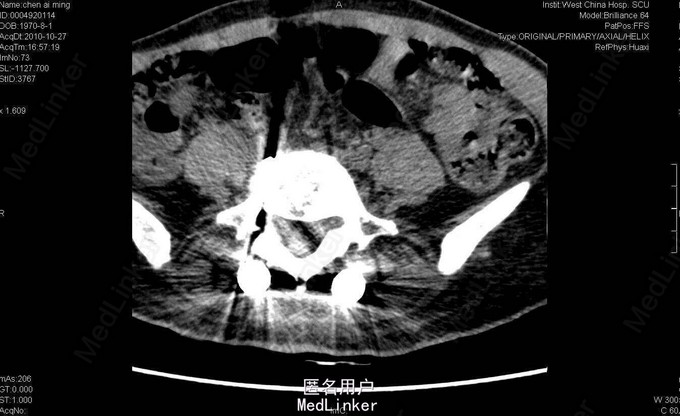

女,40岁2月,因“腰部反复疼痛2+年,加重伴双下肢疼痛、麻木1+年”入院。视:脊柱外观无畸形,皮肤未见红肿、皮疹、破溃、色斑等,无明显包块。触:腰5骶1椎棘突压痛,椎旁肌压痛,无放射痛。腰骶部感觉麻木。双下肢小腿外侧及足背感觉减退,右侧明显,其余肢体感觉正常,肌张力正常。鞍区右侧感觉减退。双下肢足背动脉搏动好。皮温正常。双膝腱减弱,踝阵挛、髌阵挛(-),巴氏征(-),右下肢直腿抬高试验(30°),直腿抬高加强试验(+),左下肢直腿抬高试验(-)。“4”字征阴性。动量:腰部不能屈伸活动,侧弯可,双下肢活动度正常,四肢肌力正常。CT及MRI:腰5骶1椎间盘脱出,腰4-5椎间盘轻度膨出,硬膜囊受压;腰5骨质增生。腰5骶1椎间盘突出症伴小关节退变。双侧椎板开窗腰5骶1椎间盘髓核摘除、内固定术。